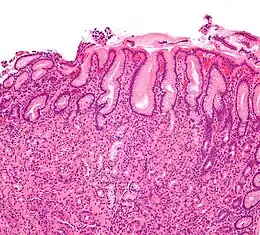

Une gastrite est une maladie inflammatoire de la paroi de l'estomac.

Le diagnostic positif de la gastrite est anatomopathologique.

La gastrite peut se diagnostiquer grâce à la clinique ou par endoscopie des voies digestives (gastroscopie). Les diagnostics différentiels sont l'ulcère gastro-duodénal et le cancer de l'estomac.